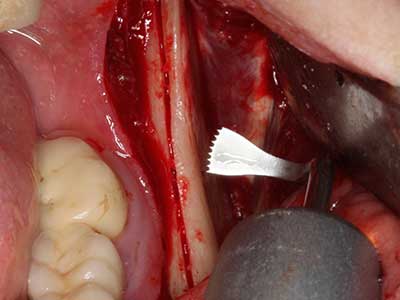

En la extracción de bloques óseos la piezocirugía también presenta ventajas adicionales: Además de la alta precisión en la osteotomía que ya se ha descrito antes, se ha comprobado que el uso de los delgados insertos de sierra resulta especialmente cuidadosas con el hueso. Frente a esto, sobre todo cuando se usan las fresas de Lindemann, cabe esperar pérdidas en la extracción significativamente más altas debido al mayor grosor de la parte frontal del cabezal (Lakshmiganthan, Gokulanathan et al. 2012). La separación basal que se necesita en particular en los injertos de bloque extraídos de forma retromolar se ve facilitada mediante sierras perpendiculares especialmente previstas a tal fin, lo que permite considerar que la cirugía piezoeléctrica es un procedimiento preciso y seguro para la obtención de bloques de hueso en el área retromolar (Happe 2007) (fig. 1-12).